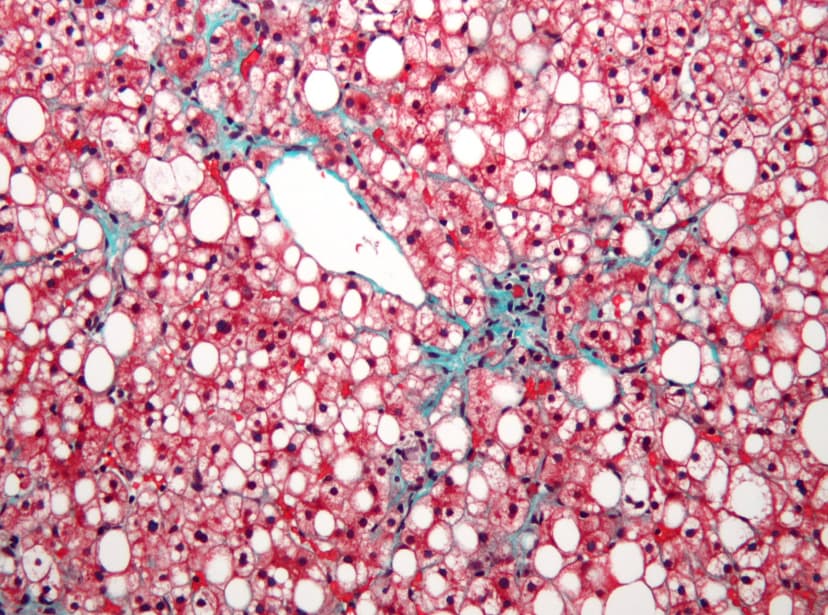

NAFLD and NASH - What It Is and How to Treat It